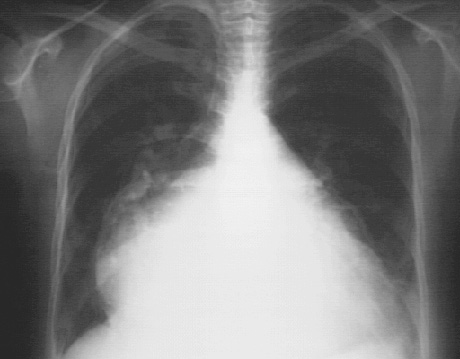

These chest X rays show marked left atrial enlargement.

In this PA view, it is demonstrated by the atrial appendage along the left heart border, and is so massive, that it also comprises the right heart border. such a giant left atrium may be seen in severe chronic mitral regurgitation.